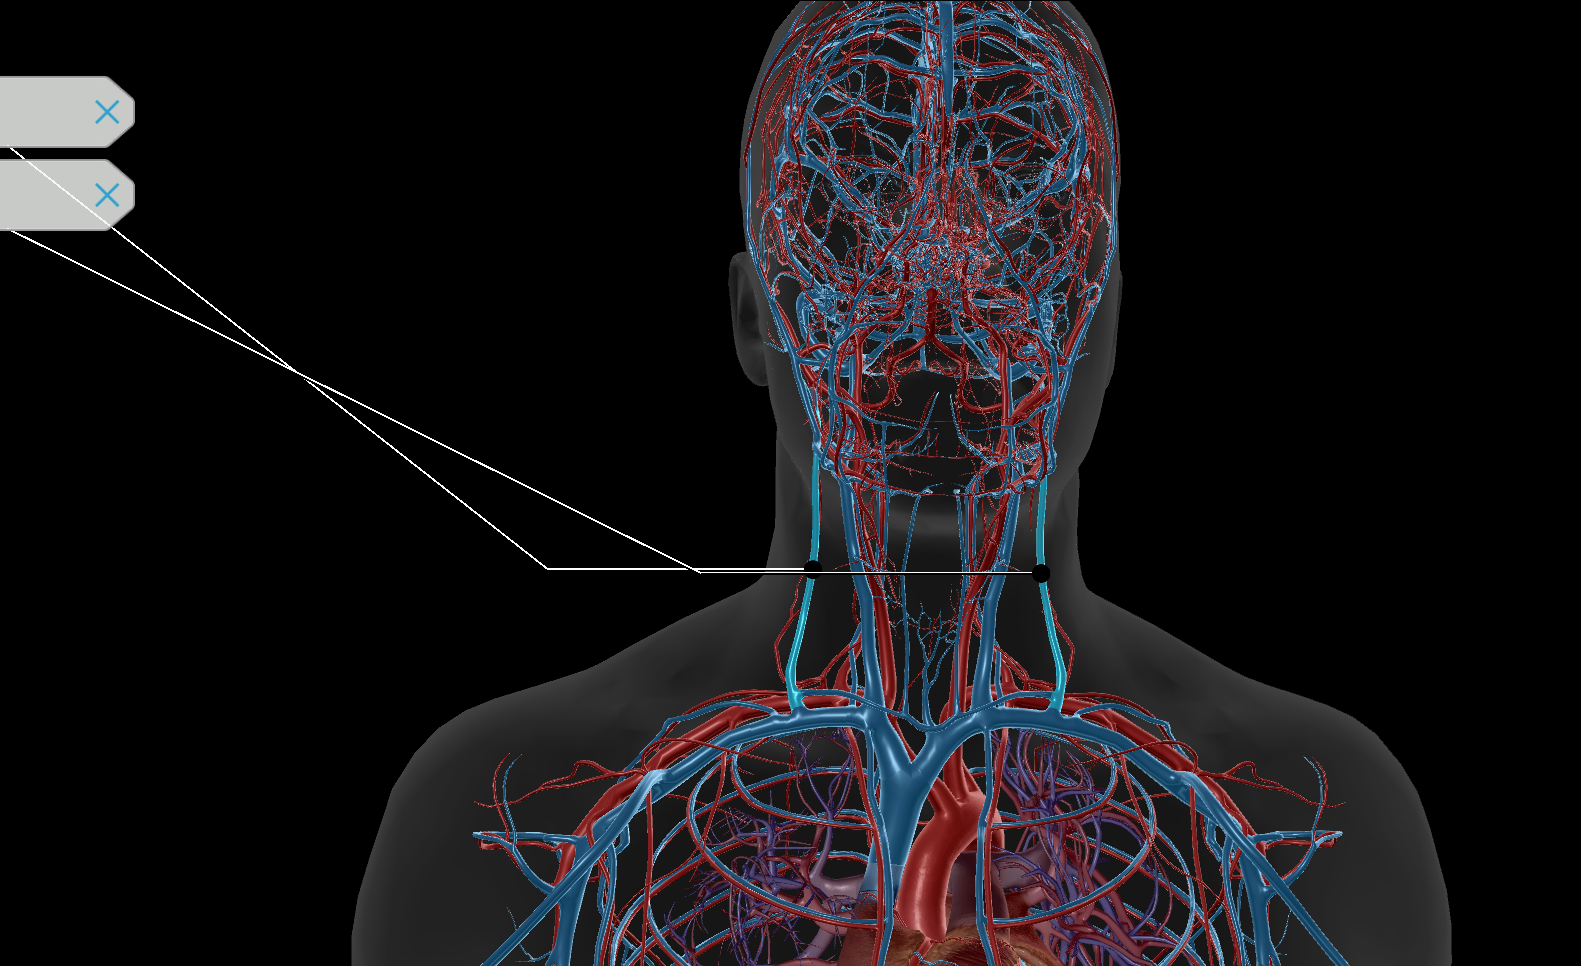

Common Carotid Artery

Internal Jugular Vein

External Jugular Vein

Brachiocephalic Vein